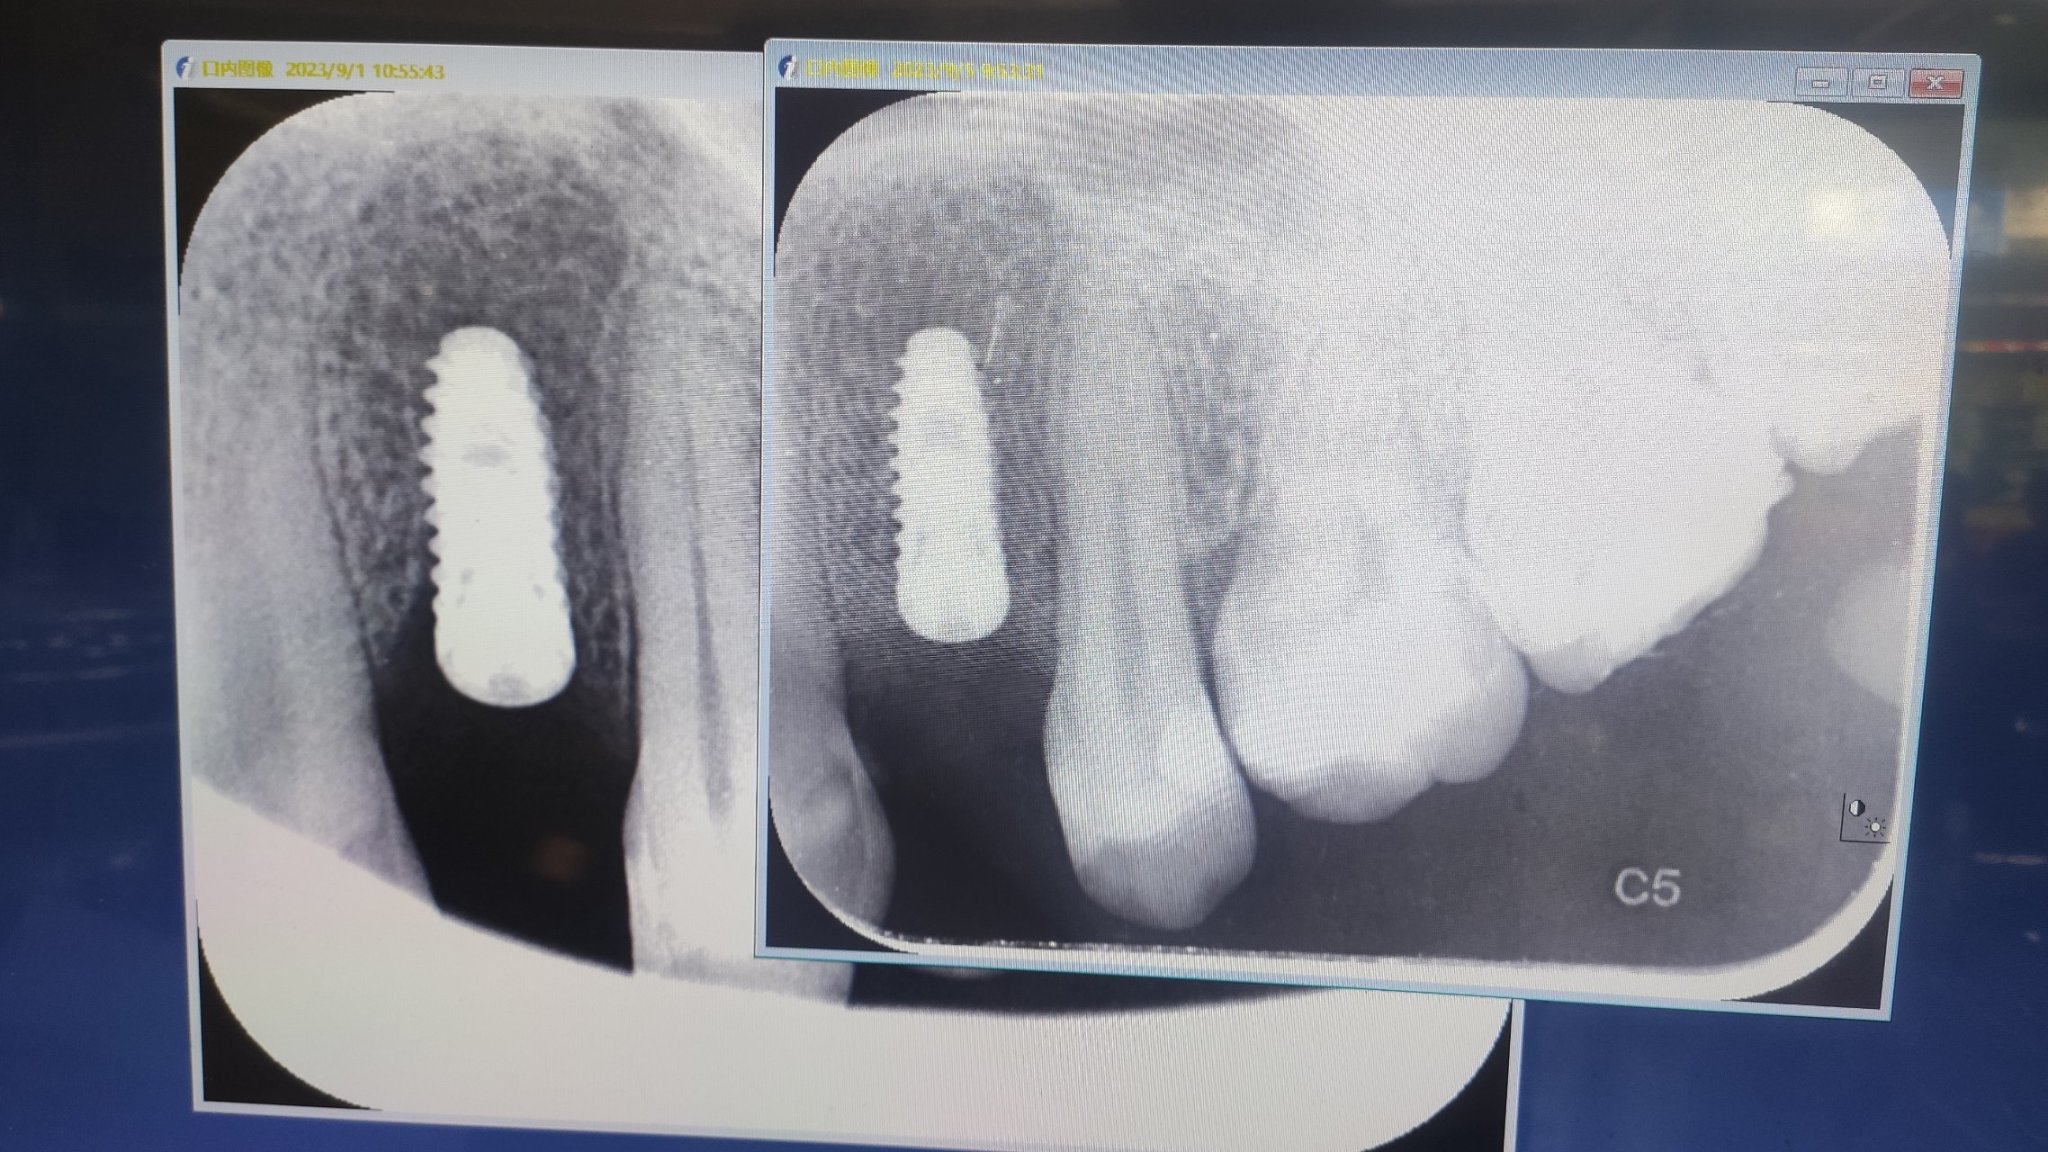

左边是发炎骨头被吸收,右边是植骨后

这里再给大家讲一下植骨后的问题,正常种植“植体”,第二天肿大的可能性比较小,实际情况还要因人而异,但是植骨多的话,基本第二天一定会肿痛,医生是让我去打吊针,然后说明一下是种牙植骨后的情况,同时也要吃消炎药(我是阿莫西林)。